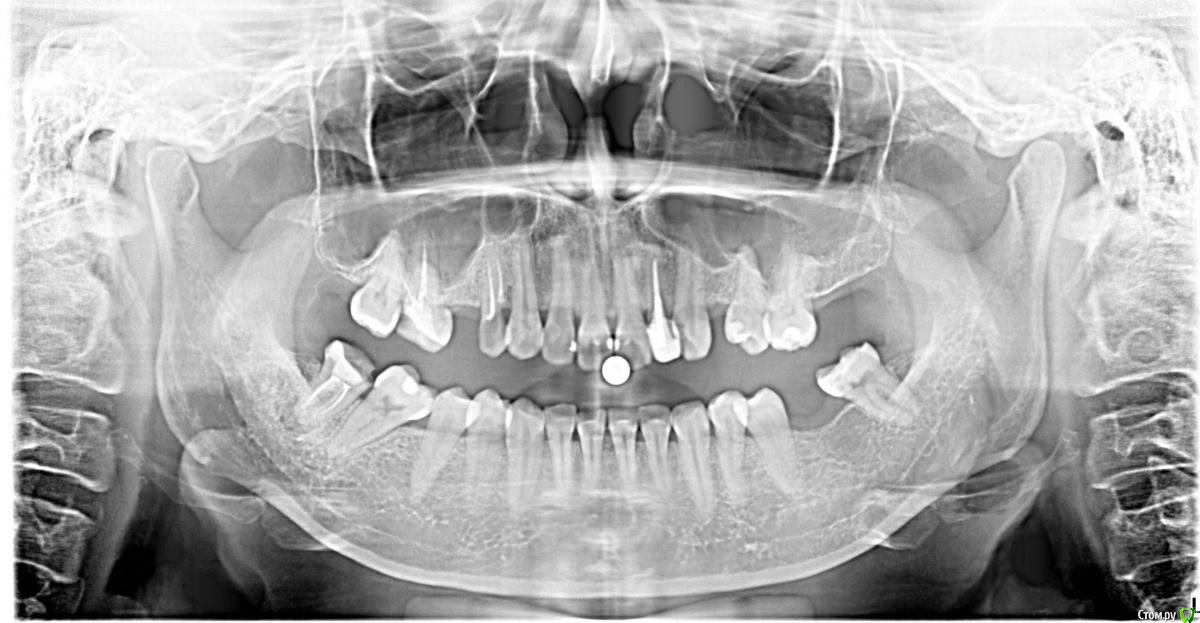

unvisage Опубликовано 29 сентября, 2017 Поделиться Опубликовано 29 сентября, 2017 (изменено) посоветуйте, пожалуйста, что делать с зубами? Изменено 29 сентября, 2017 пользователем unvisage Ссылка на комментарий